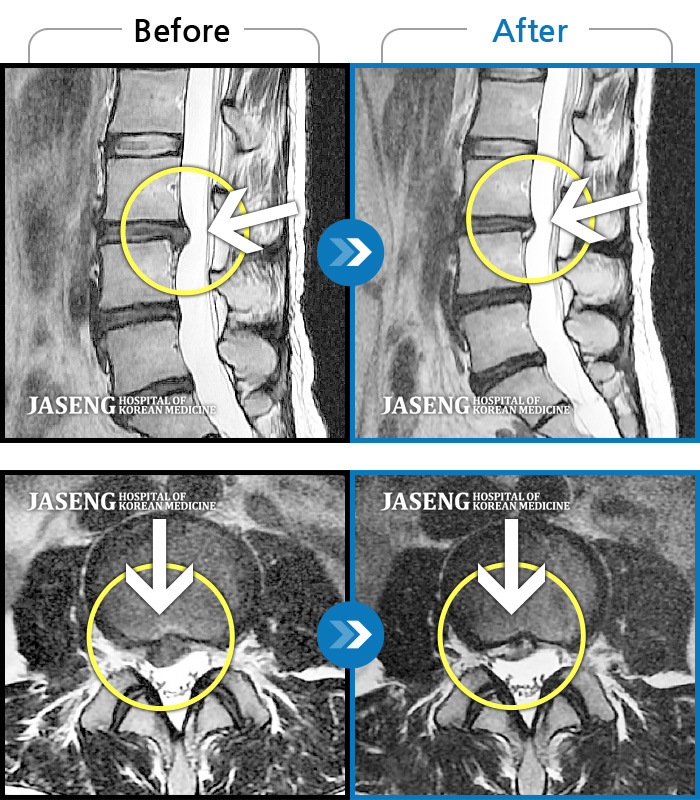

Before

After

환자에게 사전 동의를 받아 동일 조건에서 촬영되었습니다.

개인에 따라 치료 후 부작용이 발생할 수 있으니 의료진과 상담 후 치료를 진행하시기 바랍니다.

허리 양측부터 골반까지 묵직한 통증, 좌측 하지 후면으로 이어지는 당기는 통증

우측이 주로 뻐근하고 뭉친 느낌이 든다. 앉아있으면 허리가 묵직하고 목에도 무리가 와서 앉아 있을 수가 없음.